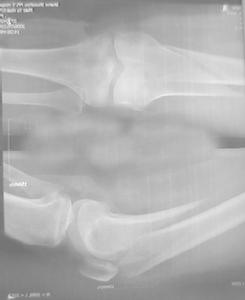

股骨髁上骨折為發生在股骨內外髁上5cm以內的骨折,不應包括內外髁部骨折和髁間骨折(AO股骨遠端A型骨折)髁上骨折一般為關節囊外骨折,而髁部骨折(股骨遠端B型骨折)及髁間骨折為關節囊內骨折但髁上骨折與髁間骨折常相互波及又稱經髁間的髁上骨折或股骨遠端C型骨折。

發病機制:股骨髁上骨折分伸展型和屈曲型,由直接暴力或間接暴力造成伸展型骨折為膝關節伸展位受傷所致,骨折線由前下至後上斜行,屈曲位受傷時,可形成由前上到後下的斜行骨折,直接暴力作用下,也可發生橫型或粉碎型骨折。目前以交通事故和工農業外傷所致高能量損傷多見,常為粉碎型髁上骨折或經髁間粉碎型骨折。

因暴力作用的方式不同而分為屈曲型和伸直型。一般以屈曲型多見。常見有橫斷、斜行,偶有粉碎骨折,易移位。

屈曲型:由於腓腸肌的牽拉,遠段向後傾倒,有損傷膕動脈的危險,近段則向前突出,在髕上囊部可刺破關節囊或皮膚。

伸直型:膝關節伸直或遭受後方暴力打擊,骨折遠端向前移位,近端向後移位,容易刺破後側的血管、神經。